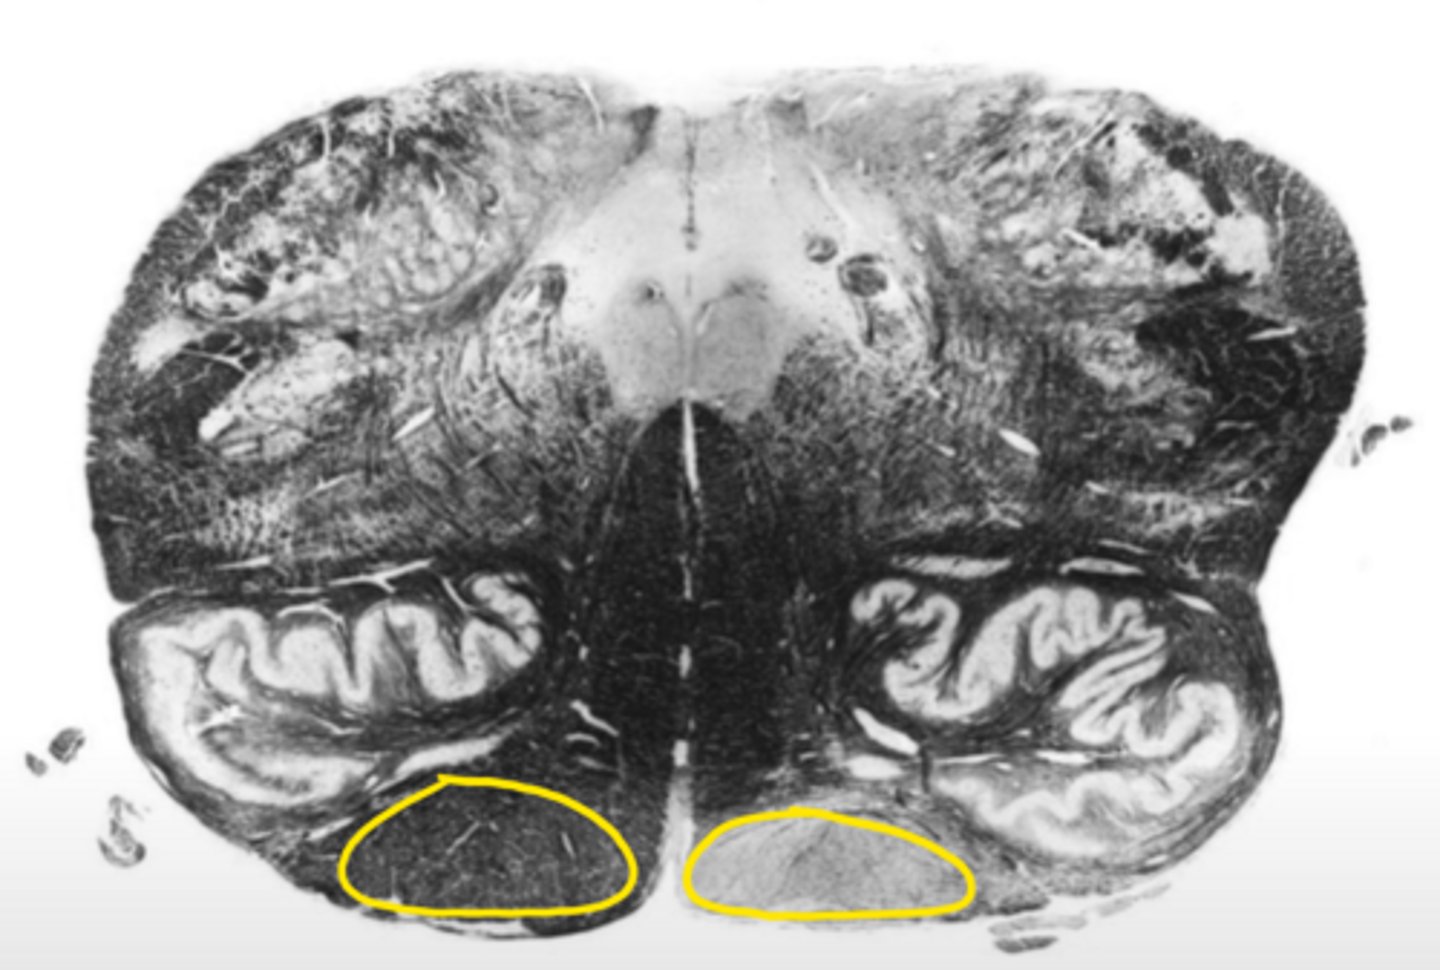

closed medulla

ID the brainstem level

central canal

ID the space